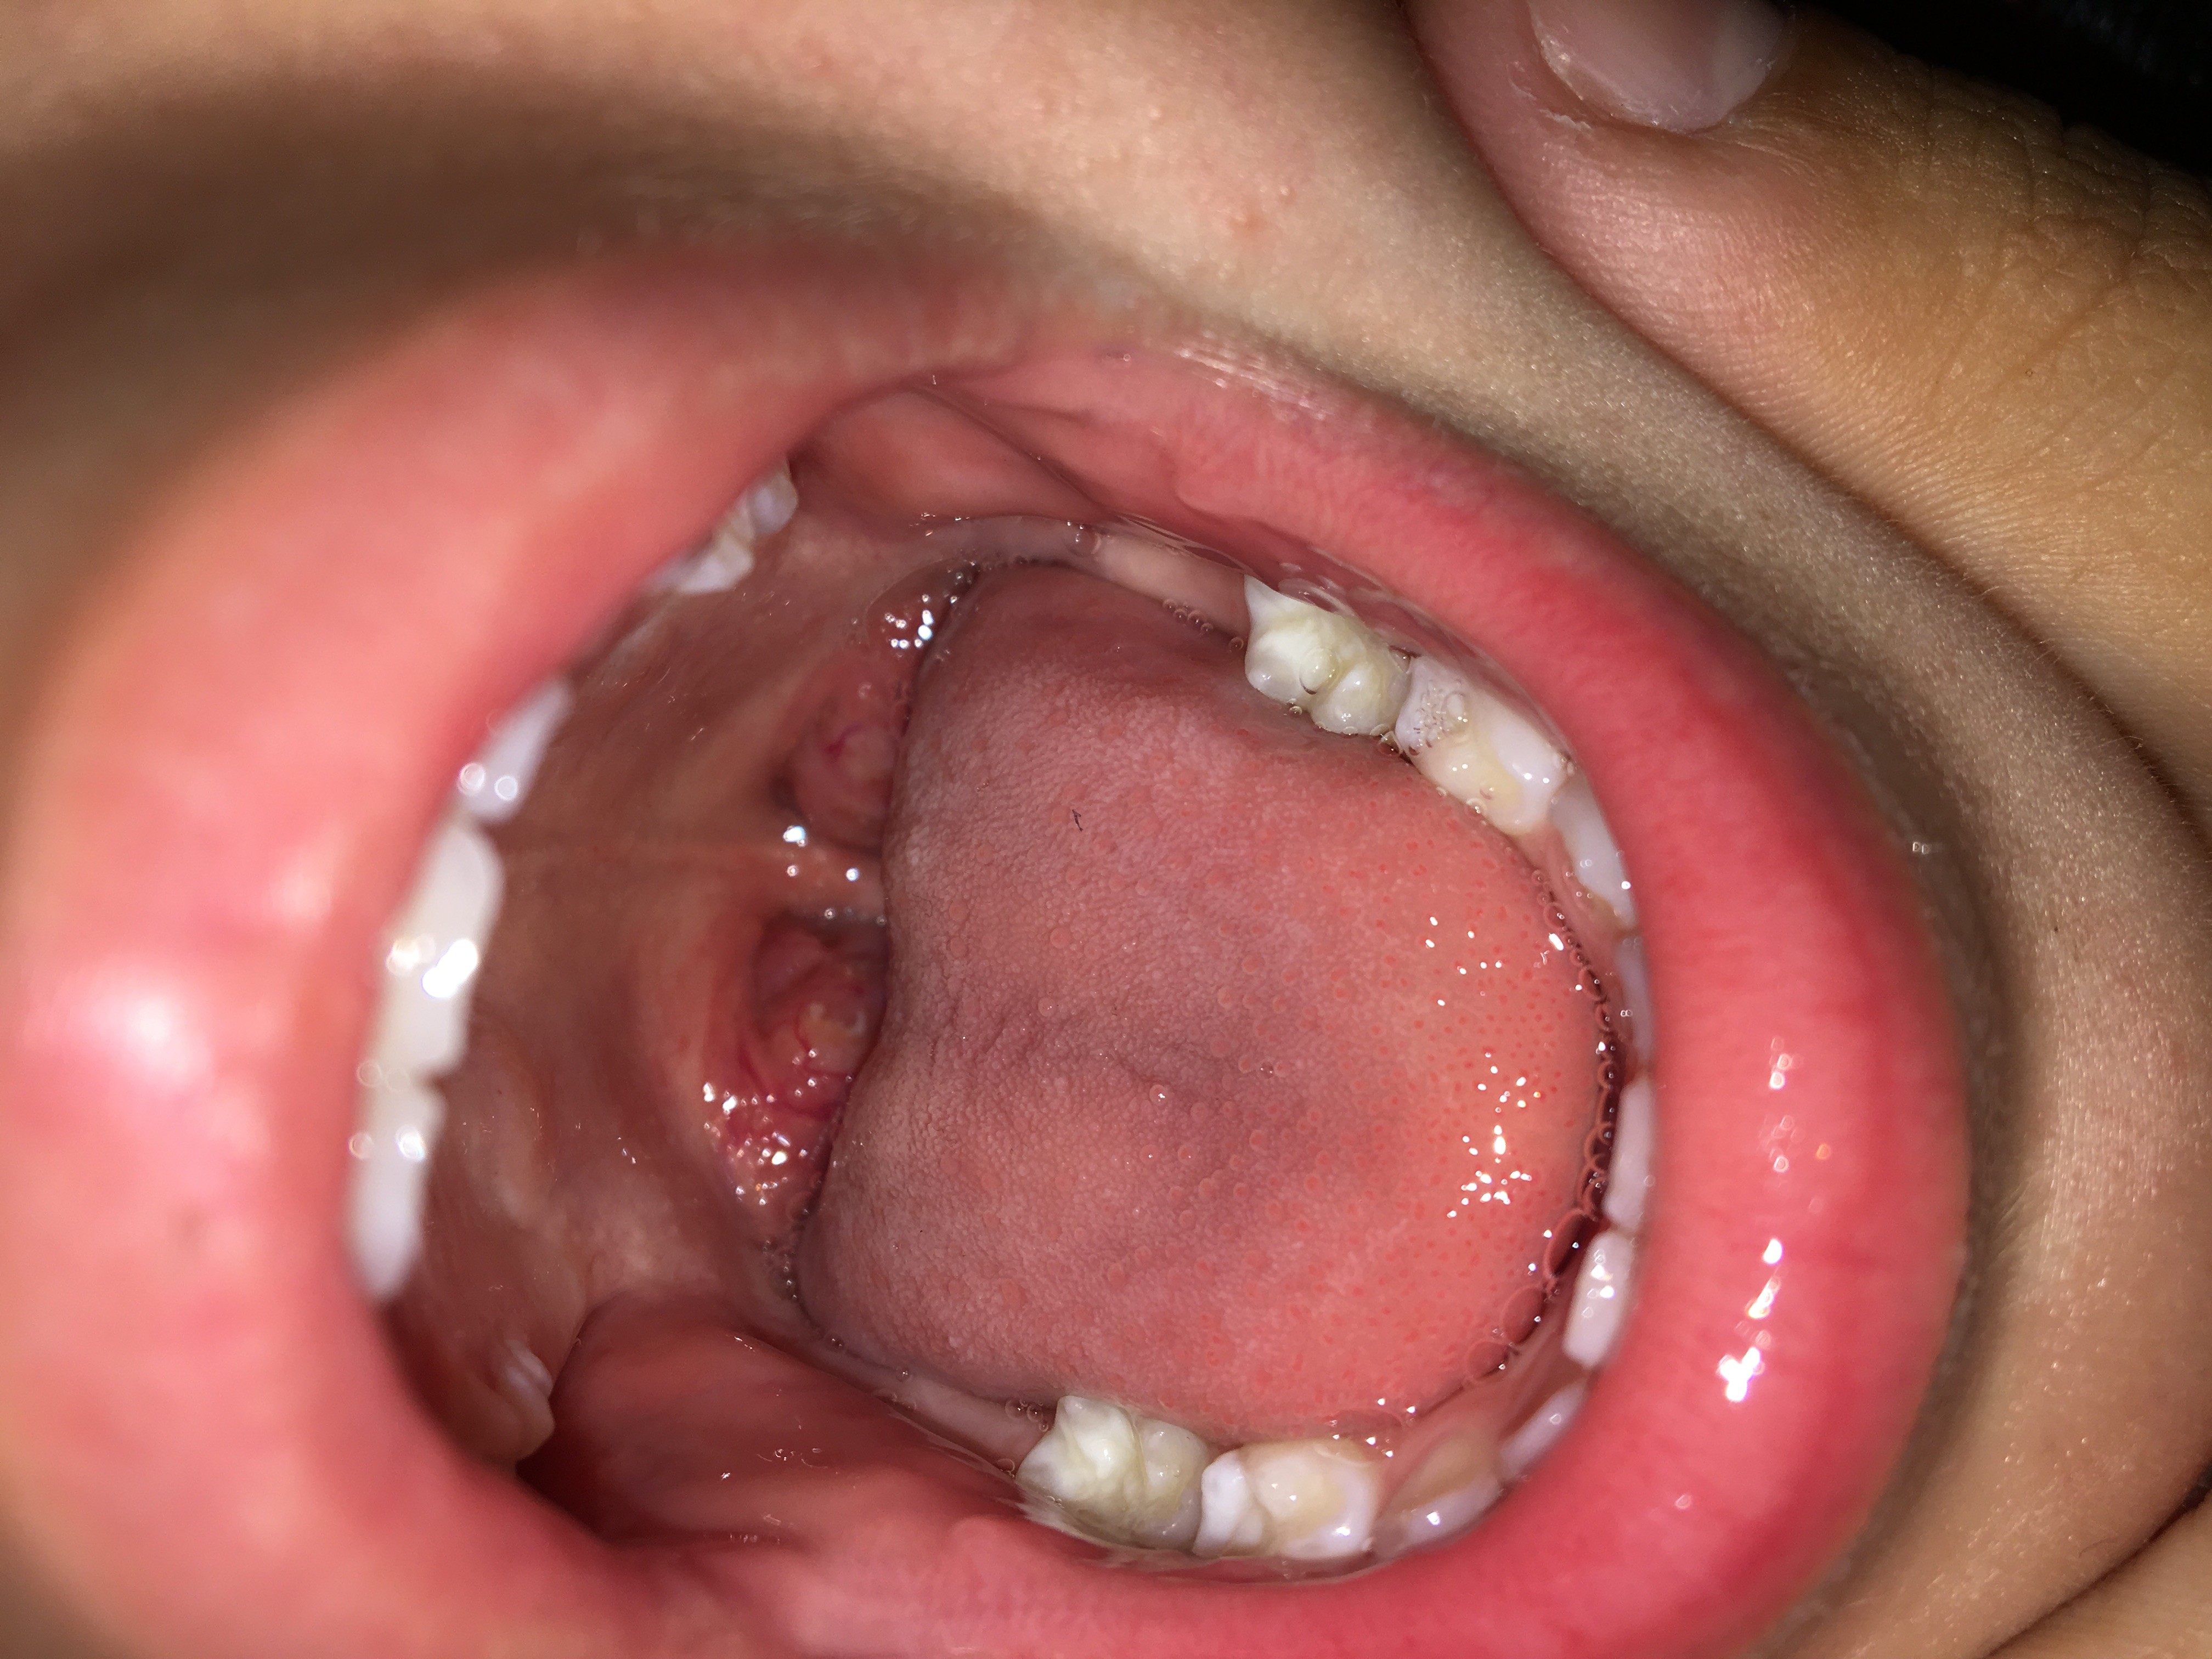

Your tonsils are located in the back of your throat. They’re the two round lumps of tissue you see when you open your mouth wide. You can’t easily see your adenoids, but they’re found in the upper part of your nasal cavity.

Both your tonsils and adenoids help to trap pathogens, such as bacteria or viruses, that enter your mouth or nose. They contain immune cells that produce antibodies that kill these pathogens before they can spread to the rest of your body.

Tonsils and adenoids often become enlarged or inflamed when they’re fighting a pathogen. However, some children have enlarged tonsils and adenoids without any underlying cause. Experts aren’t sure why this happens, but there may be a genetic link.

When your tonsils and adenoids are enlarged, you may have other symptoms as well, such as: